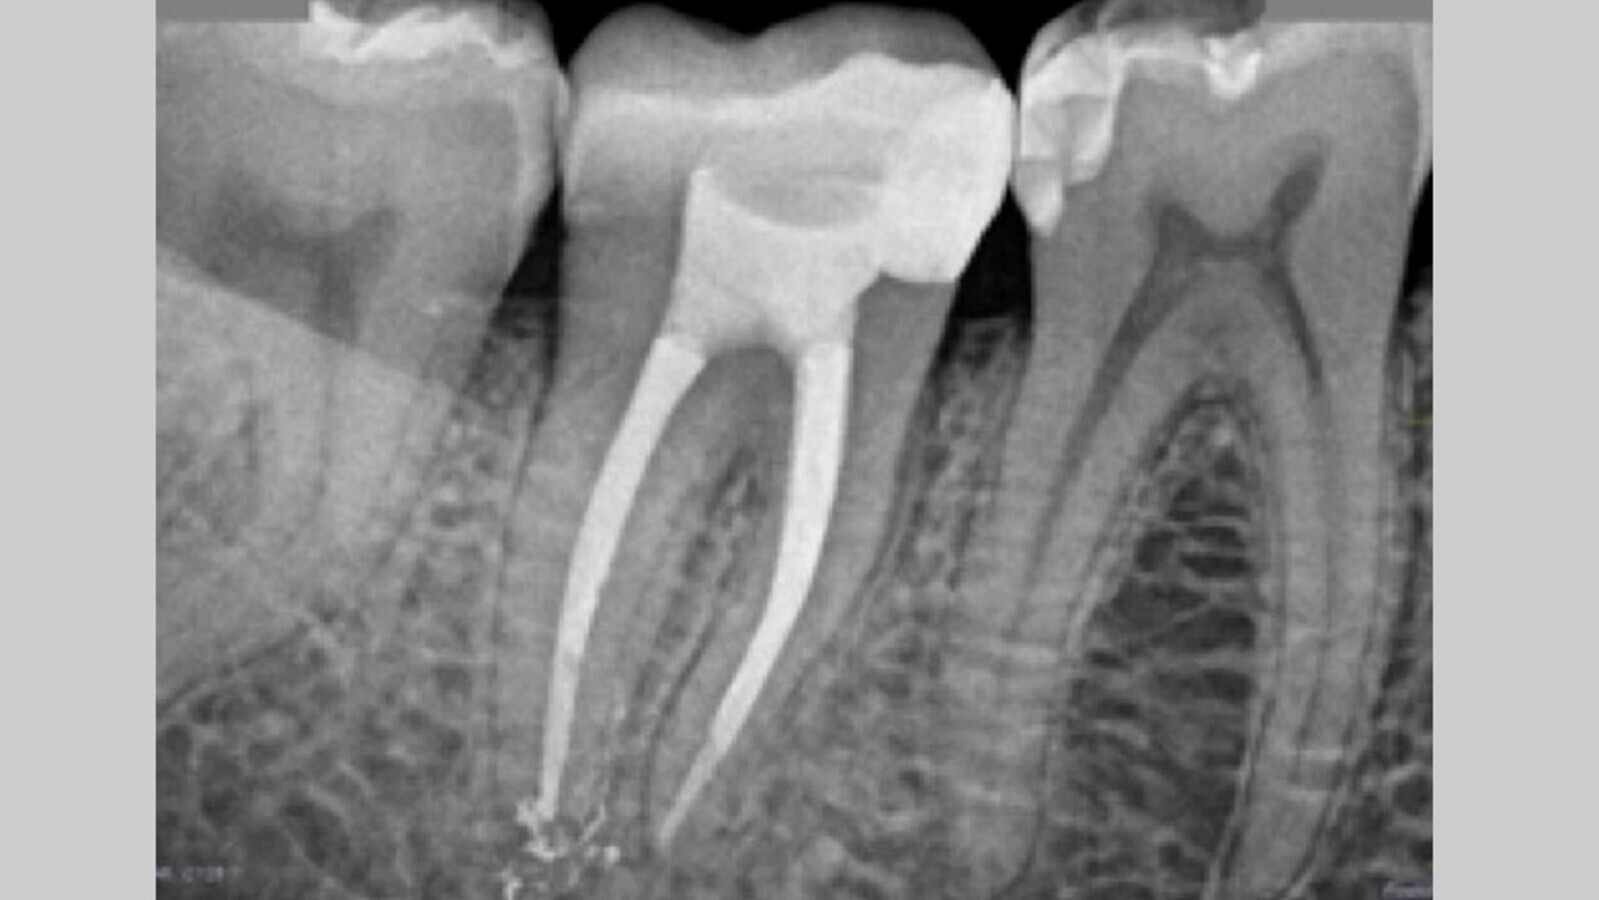

Una vez conformado e irrigado el sistema de conductos, se realiza la selección del material de obturación. En este caso se calibran 3 conos Autofit 04 (SybronEndo greater taper) y se comprueba la adaptación mediante una radiografía de conometría (Fig. 4).

Fig. 4. Radiografía periapical de conometría.

Una vez confirmada la perfecta adaptación del material de obturación, se introducen los conos calibrados recubiertos en una fina película de cemento resinoso AHPLUS (Dentsply, Sirona) y escogemos una técnica termoplástica como técnica de obturación, concretamente con el uso de termocompactadores (Fig. 5).

Fig. 5. Radiografía periapical final de la endodoncia del 4.7.